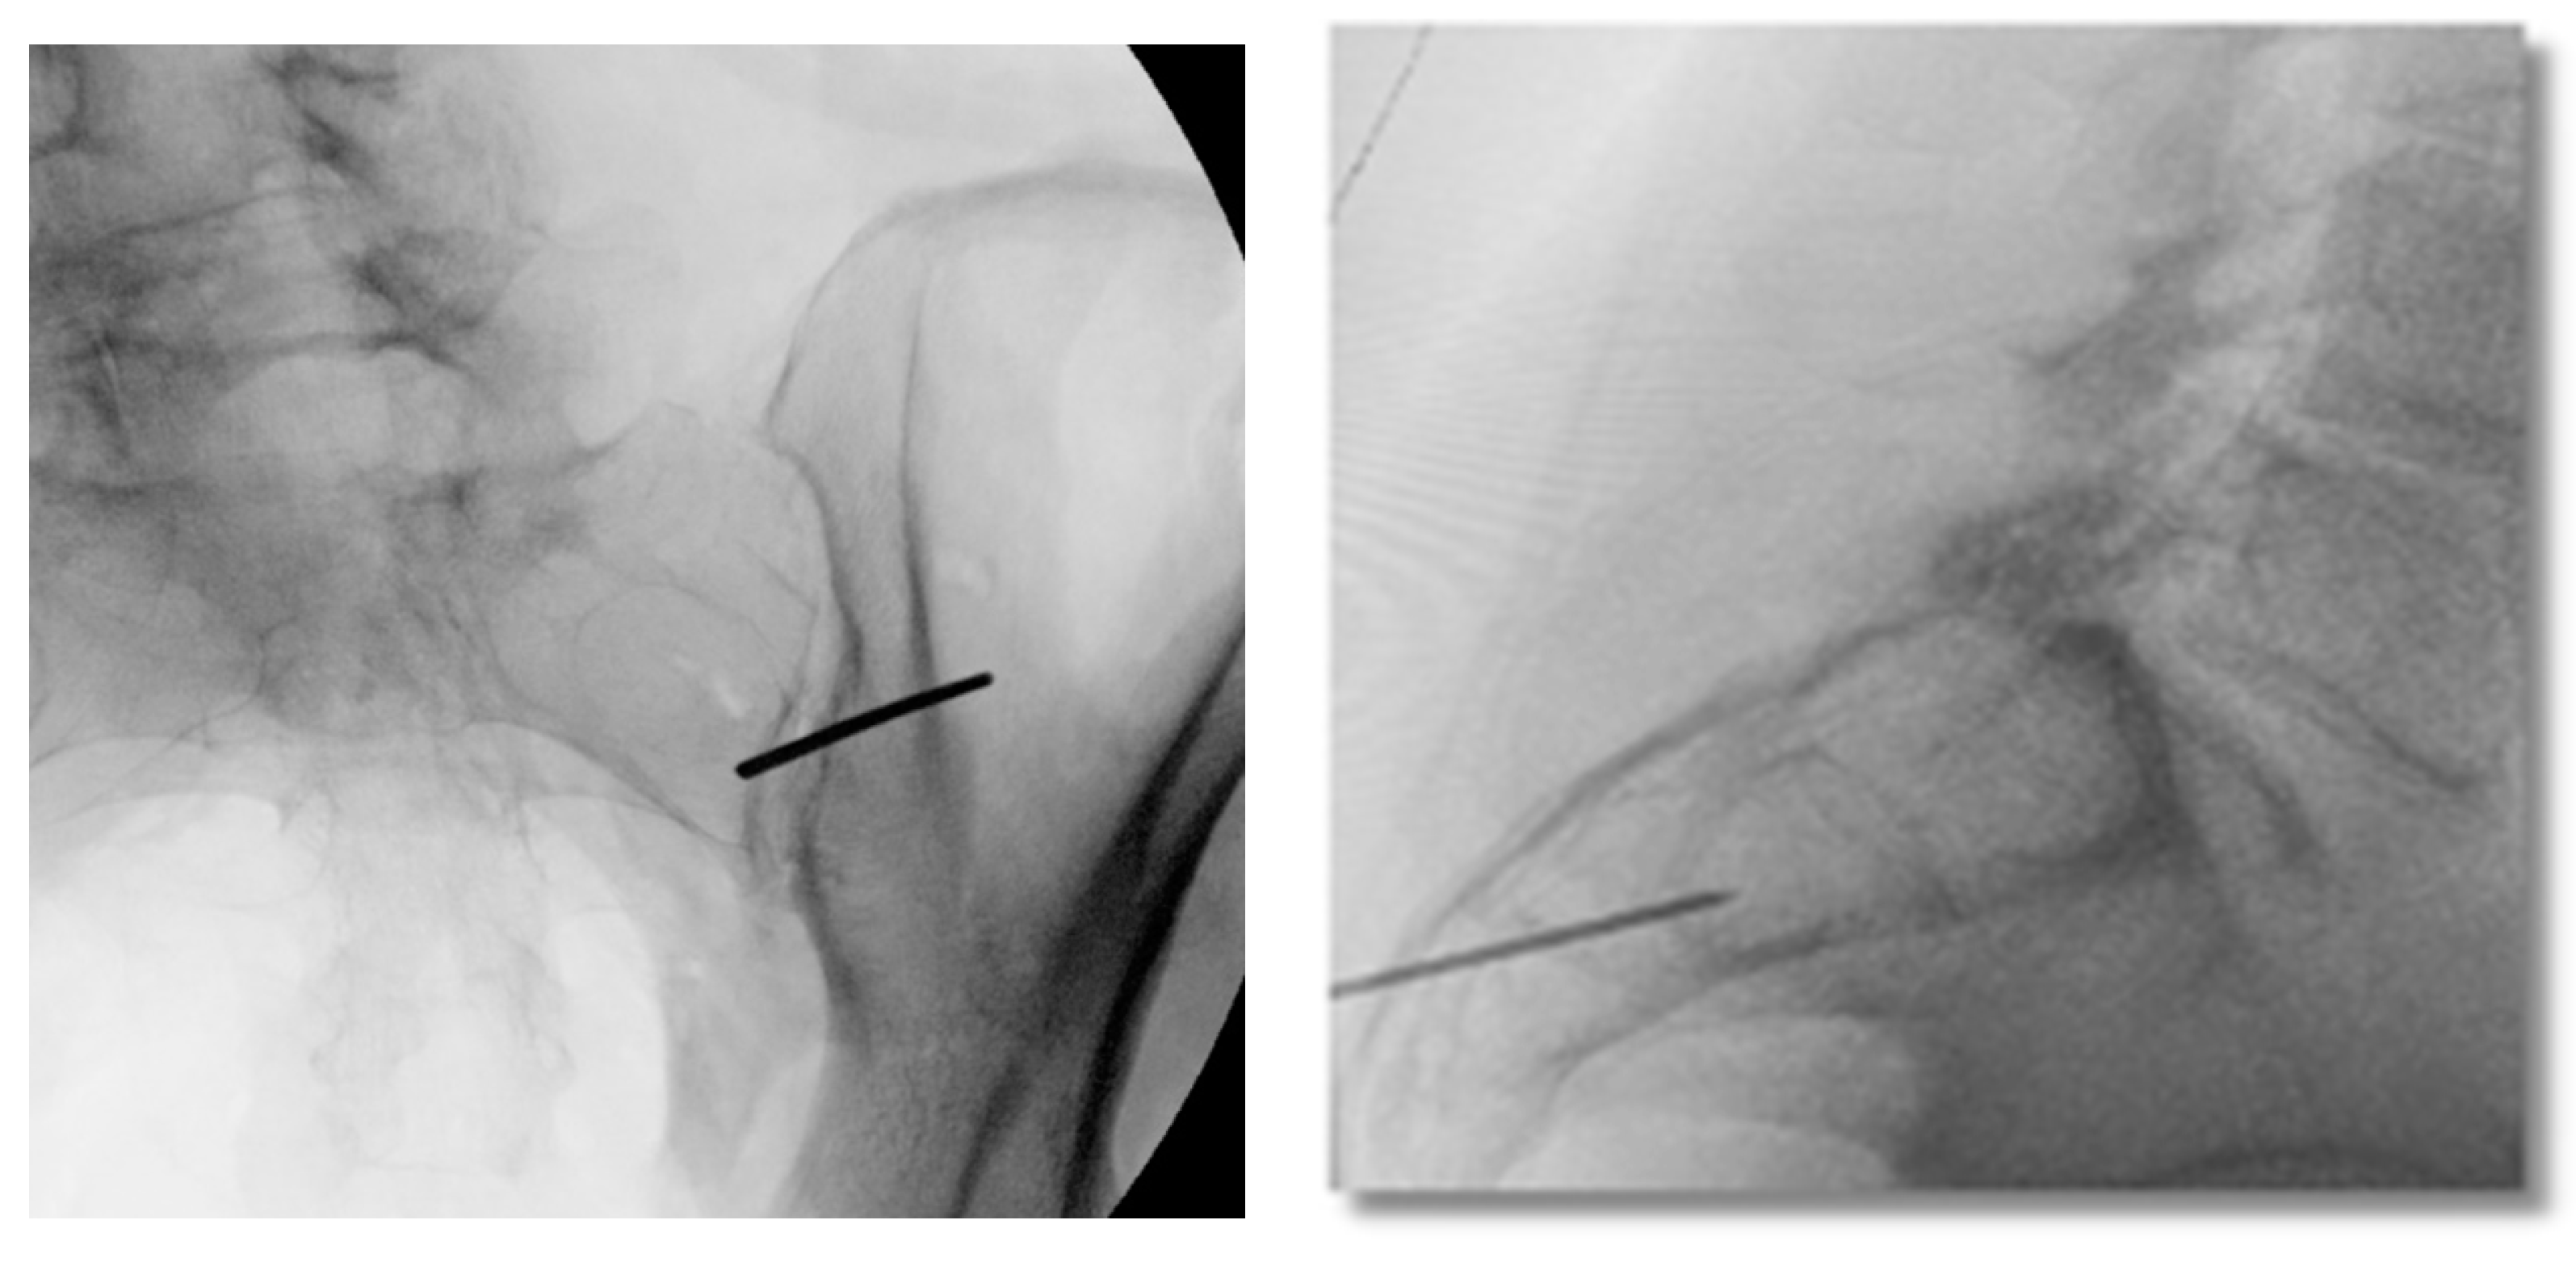

Figure 5. Oblique inlet (left) fluoroscopic views are used to verify implant preparation space using a reamer-drill visualized in the lateral view (right).

A mechanically solid implant construct is imperative to short-term stabilization of the joint. As such, a proper implant bed must be prepared for the construct, utilizing a Reamer-Drill. Oblique and inlet views should be used to confirm optimal trajectory of instrumentation. There must be adequate room ventral to the instrumentation to ensure that the Reamer-Drill does not violate the anterior border of the inferior joint line. (Figure 5). Utilizing inlet and lateral views, an implant bed should be created by advancing the Reamer-Drill over the Initial Dilator and reaming down to the dense cortical bone of the ilium (Figure 5). The tip of the Reamer-Drill should pass the posterior-inferior border of the ilium in lateral view to ensure that the implant bed is properly prepared.